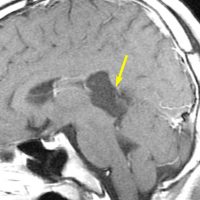

なぜ脳幹部からの無理な剥離が必要な手術を勧めるか

30歳くらいの時に初回の開頭手術で部分摘出を受けて,現在70代の患者さんの画像です。黄色は今も残っている腫瘍です。2度目の開頭手術,3度目の開頭手術では癒着で脳幹部や脳神経からの剥離が全くできませんでした。現在でも脳幹部に入り込むように腫瘍がゆっくり大きくなっていて,体幹失調のために車椅子生活です。顔面神経麻痺,嚥下障害,構語障害,眼球運動障害などもあります。髄液吸収障害による水頭症を併発してシャント手術も受けています。

この患者さんの40年の経過はいろいろなことを教えてくれます。似たような患者さんをたくさん見てくると,初回手術で取りきれなかった類表皮のう胞を,2度目の開頭手術で完全摘出することはとても難しいという経験を積みます。

数十年後のことを考えるのであれば,初回手術で完全摘出するべきです